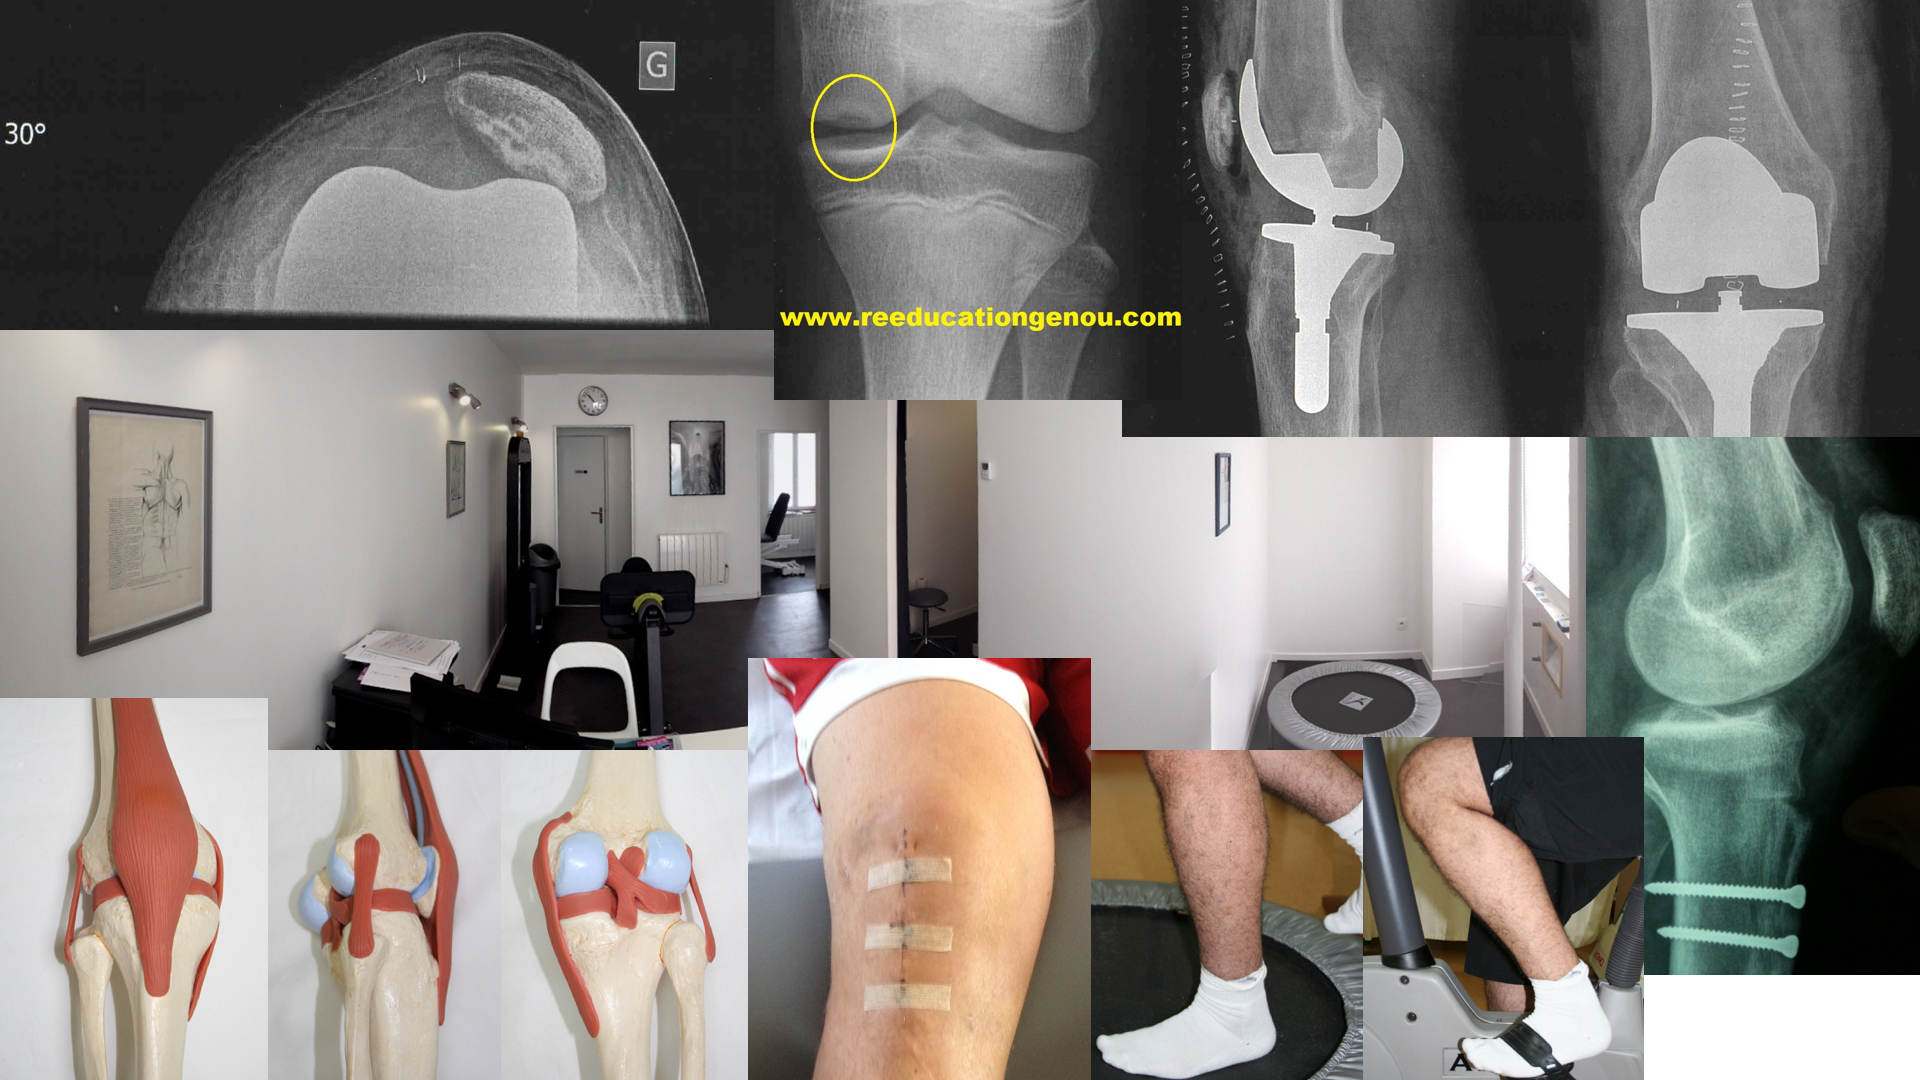

2 points d'arthroscopie + site de DiDt (ici méthode TLS)

merci Dr Nicolas LEFEVRE (Clinique du sport paris 5) pour cette superbe cicatrice genou droit